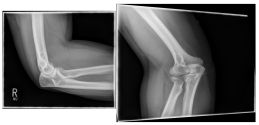

Photo: An undislocated fracture that can be treated conservatively.